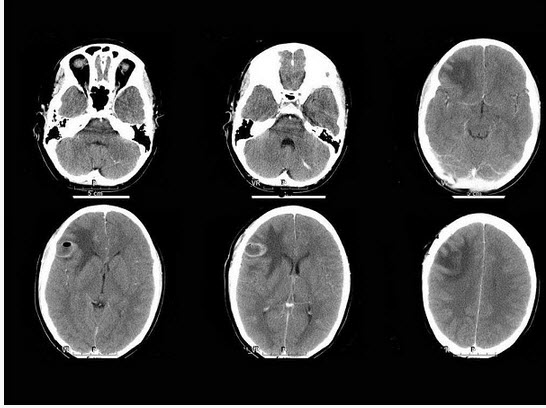

B.胆囊缩小

男,74岁,外伤1小时,意识模糊,平扫CT检查如图,最可能的诊断为()

A.硬膜外血肿

B.硬膜下血肿

C.蛛网膜下腔出血

D.脑内血肿